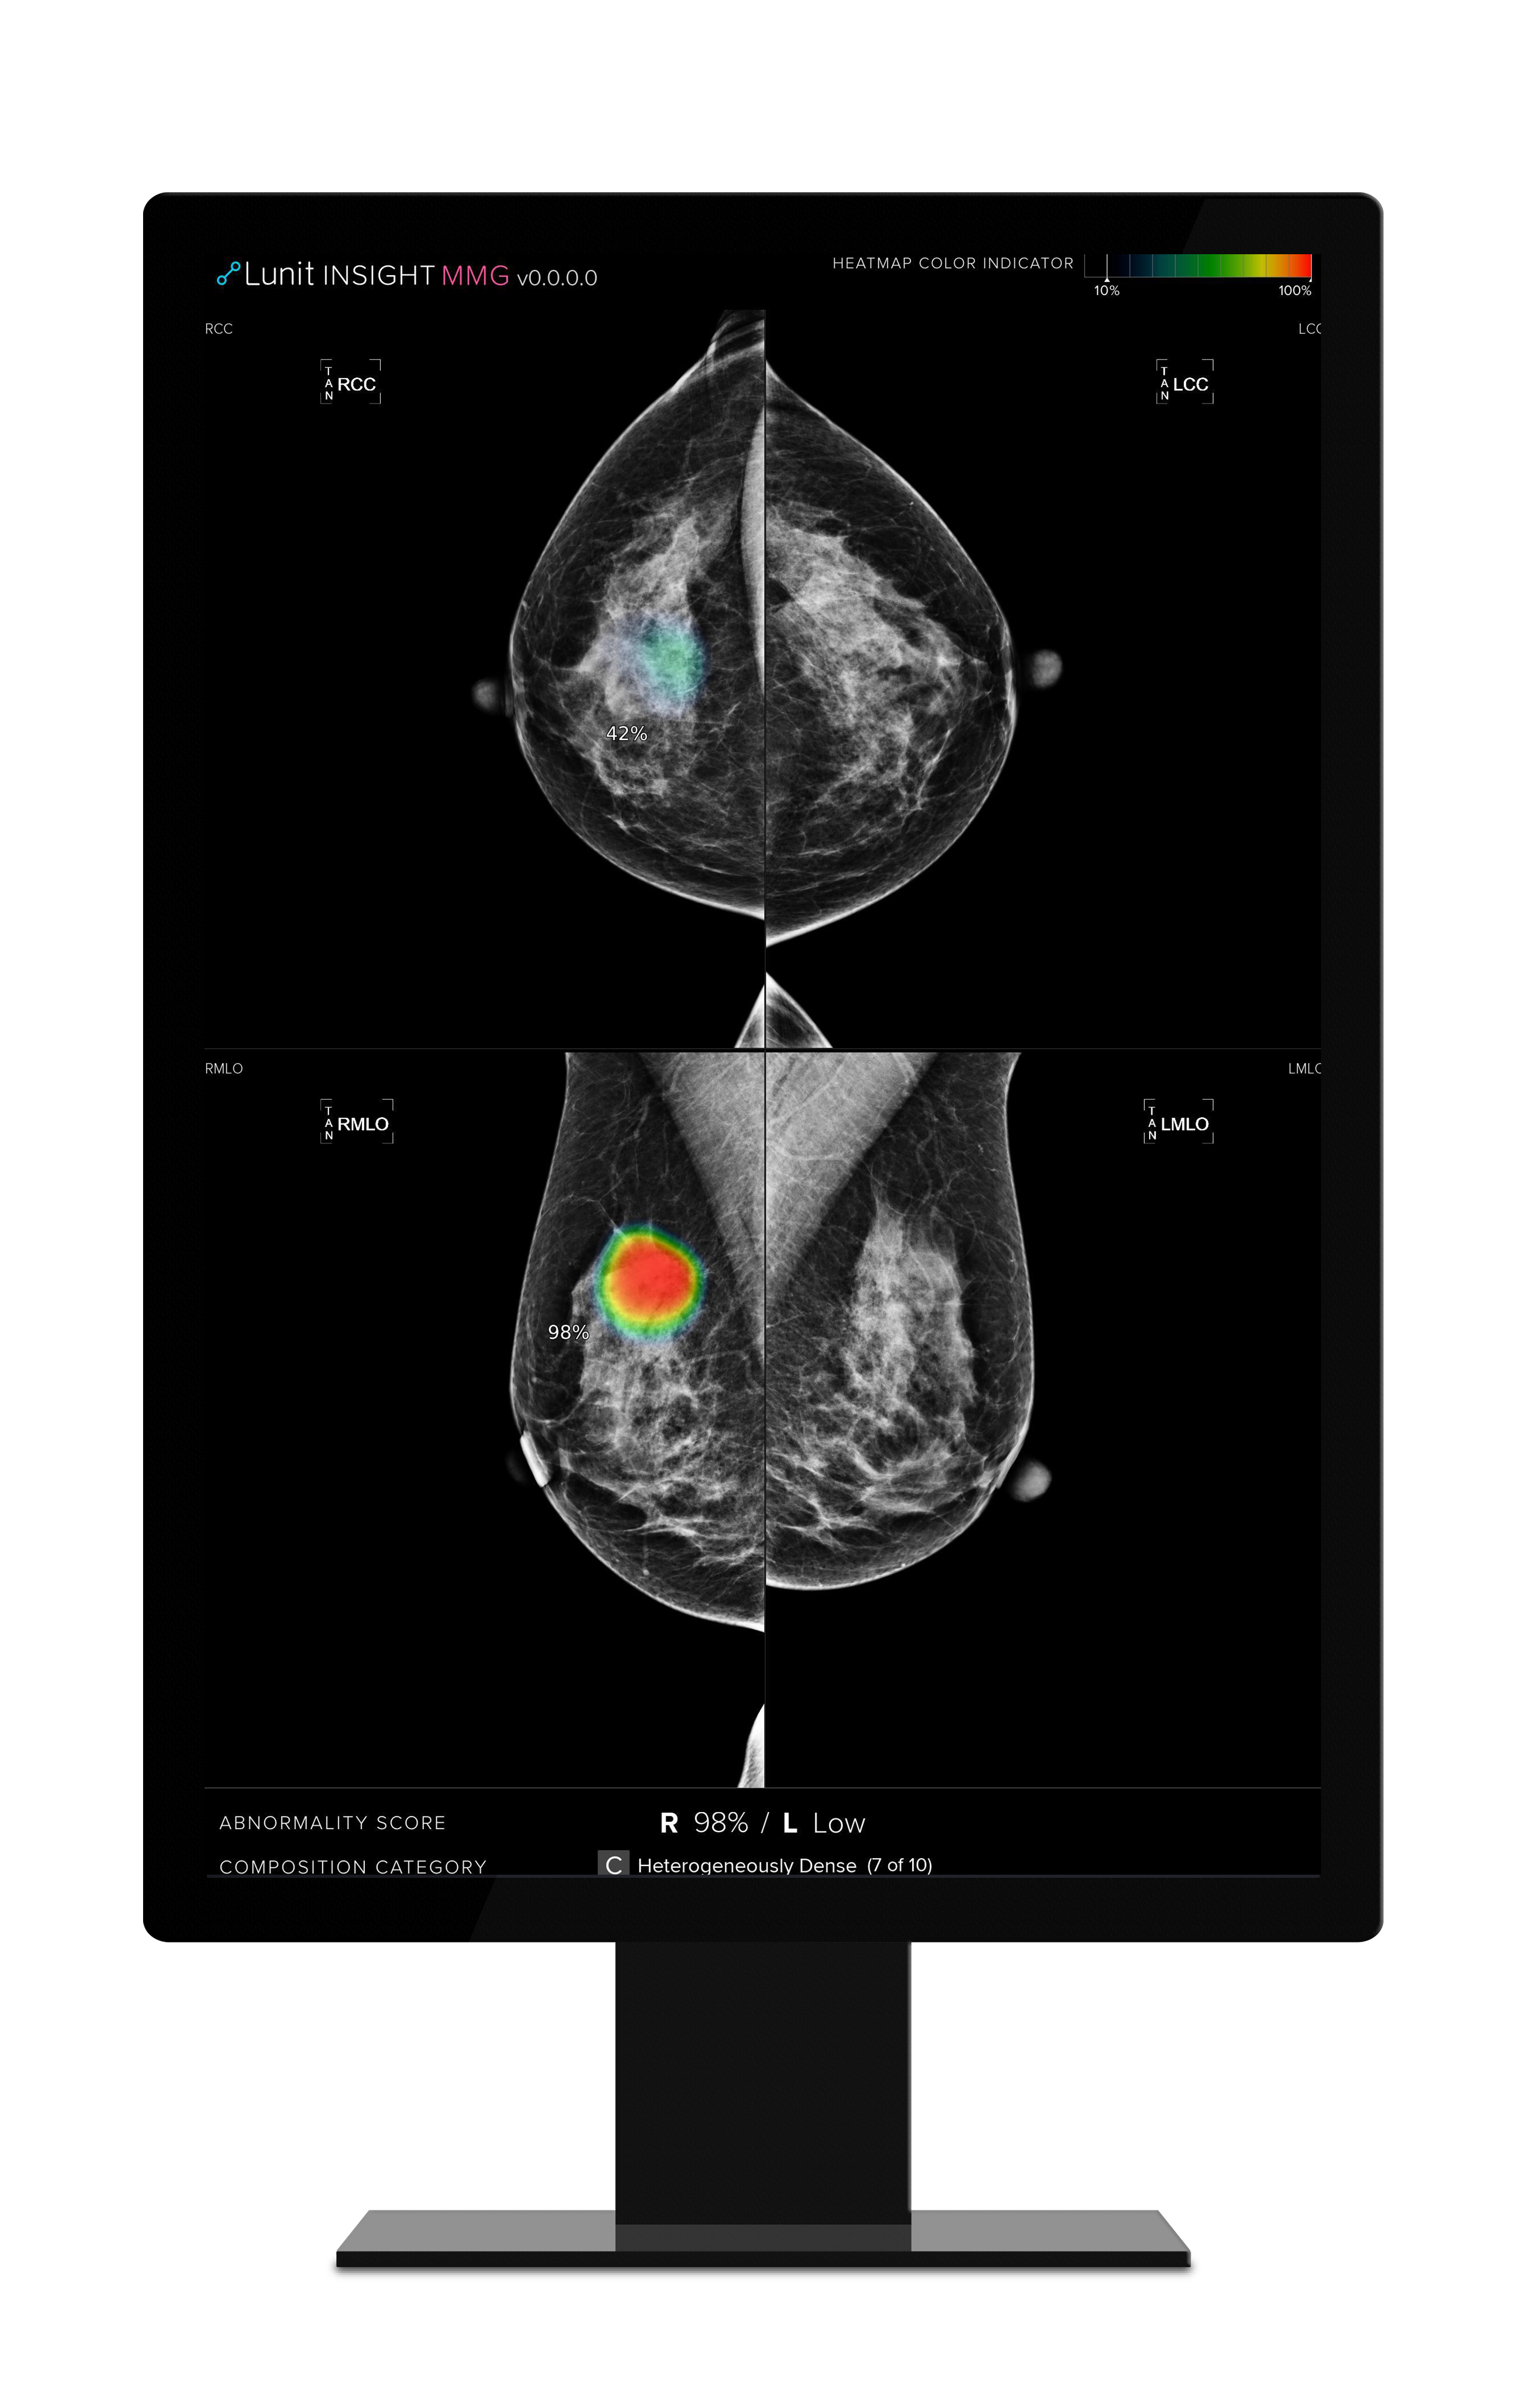

Along with Lunit’s AI solution for chest x-rays, Lunit INSIGHT MMG is one of the company’s most mature radiology products, analyzing mammography images with high speed and 96% accuracy. The product is trained with more than 240,000 data sets, including over 50,000 biopsy-proven breast cancer cases, and has shown to reduce the chances of undetected breast cancer cases by 50% in mammogram screenings.

▲Lunit INSIGHT MMG